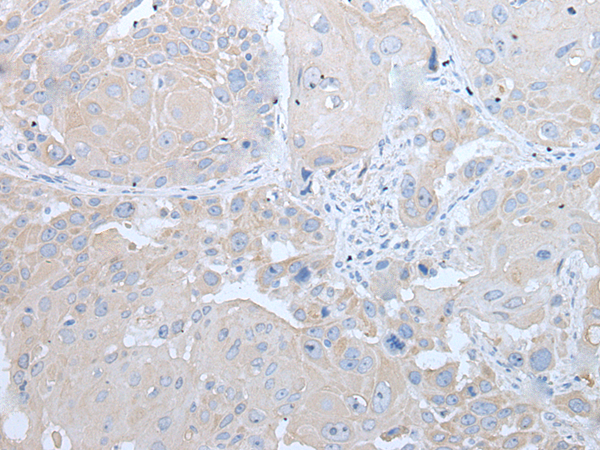

分类: 科研抗体货号: P12760别名: HHF5; CD220应用: IHC反应种属: Human, Mouse, Rat